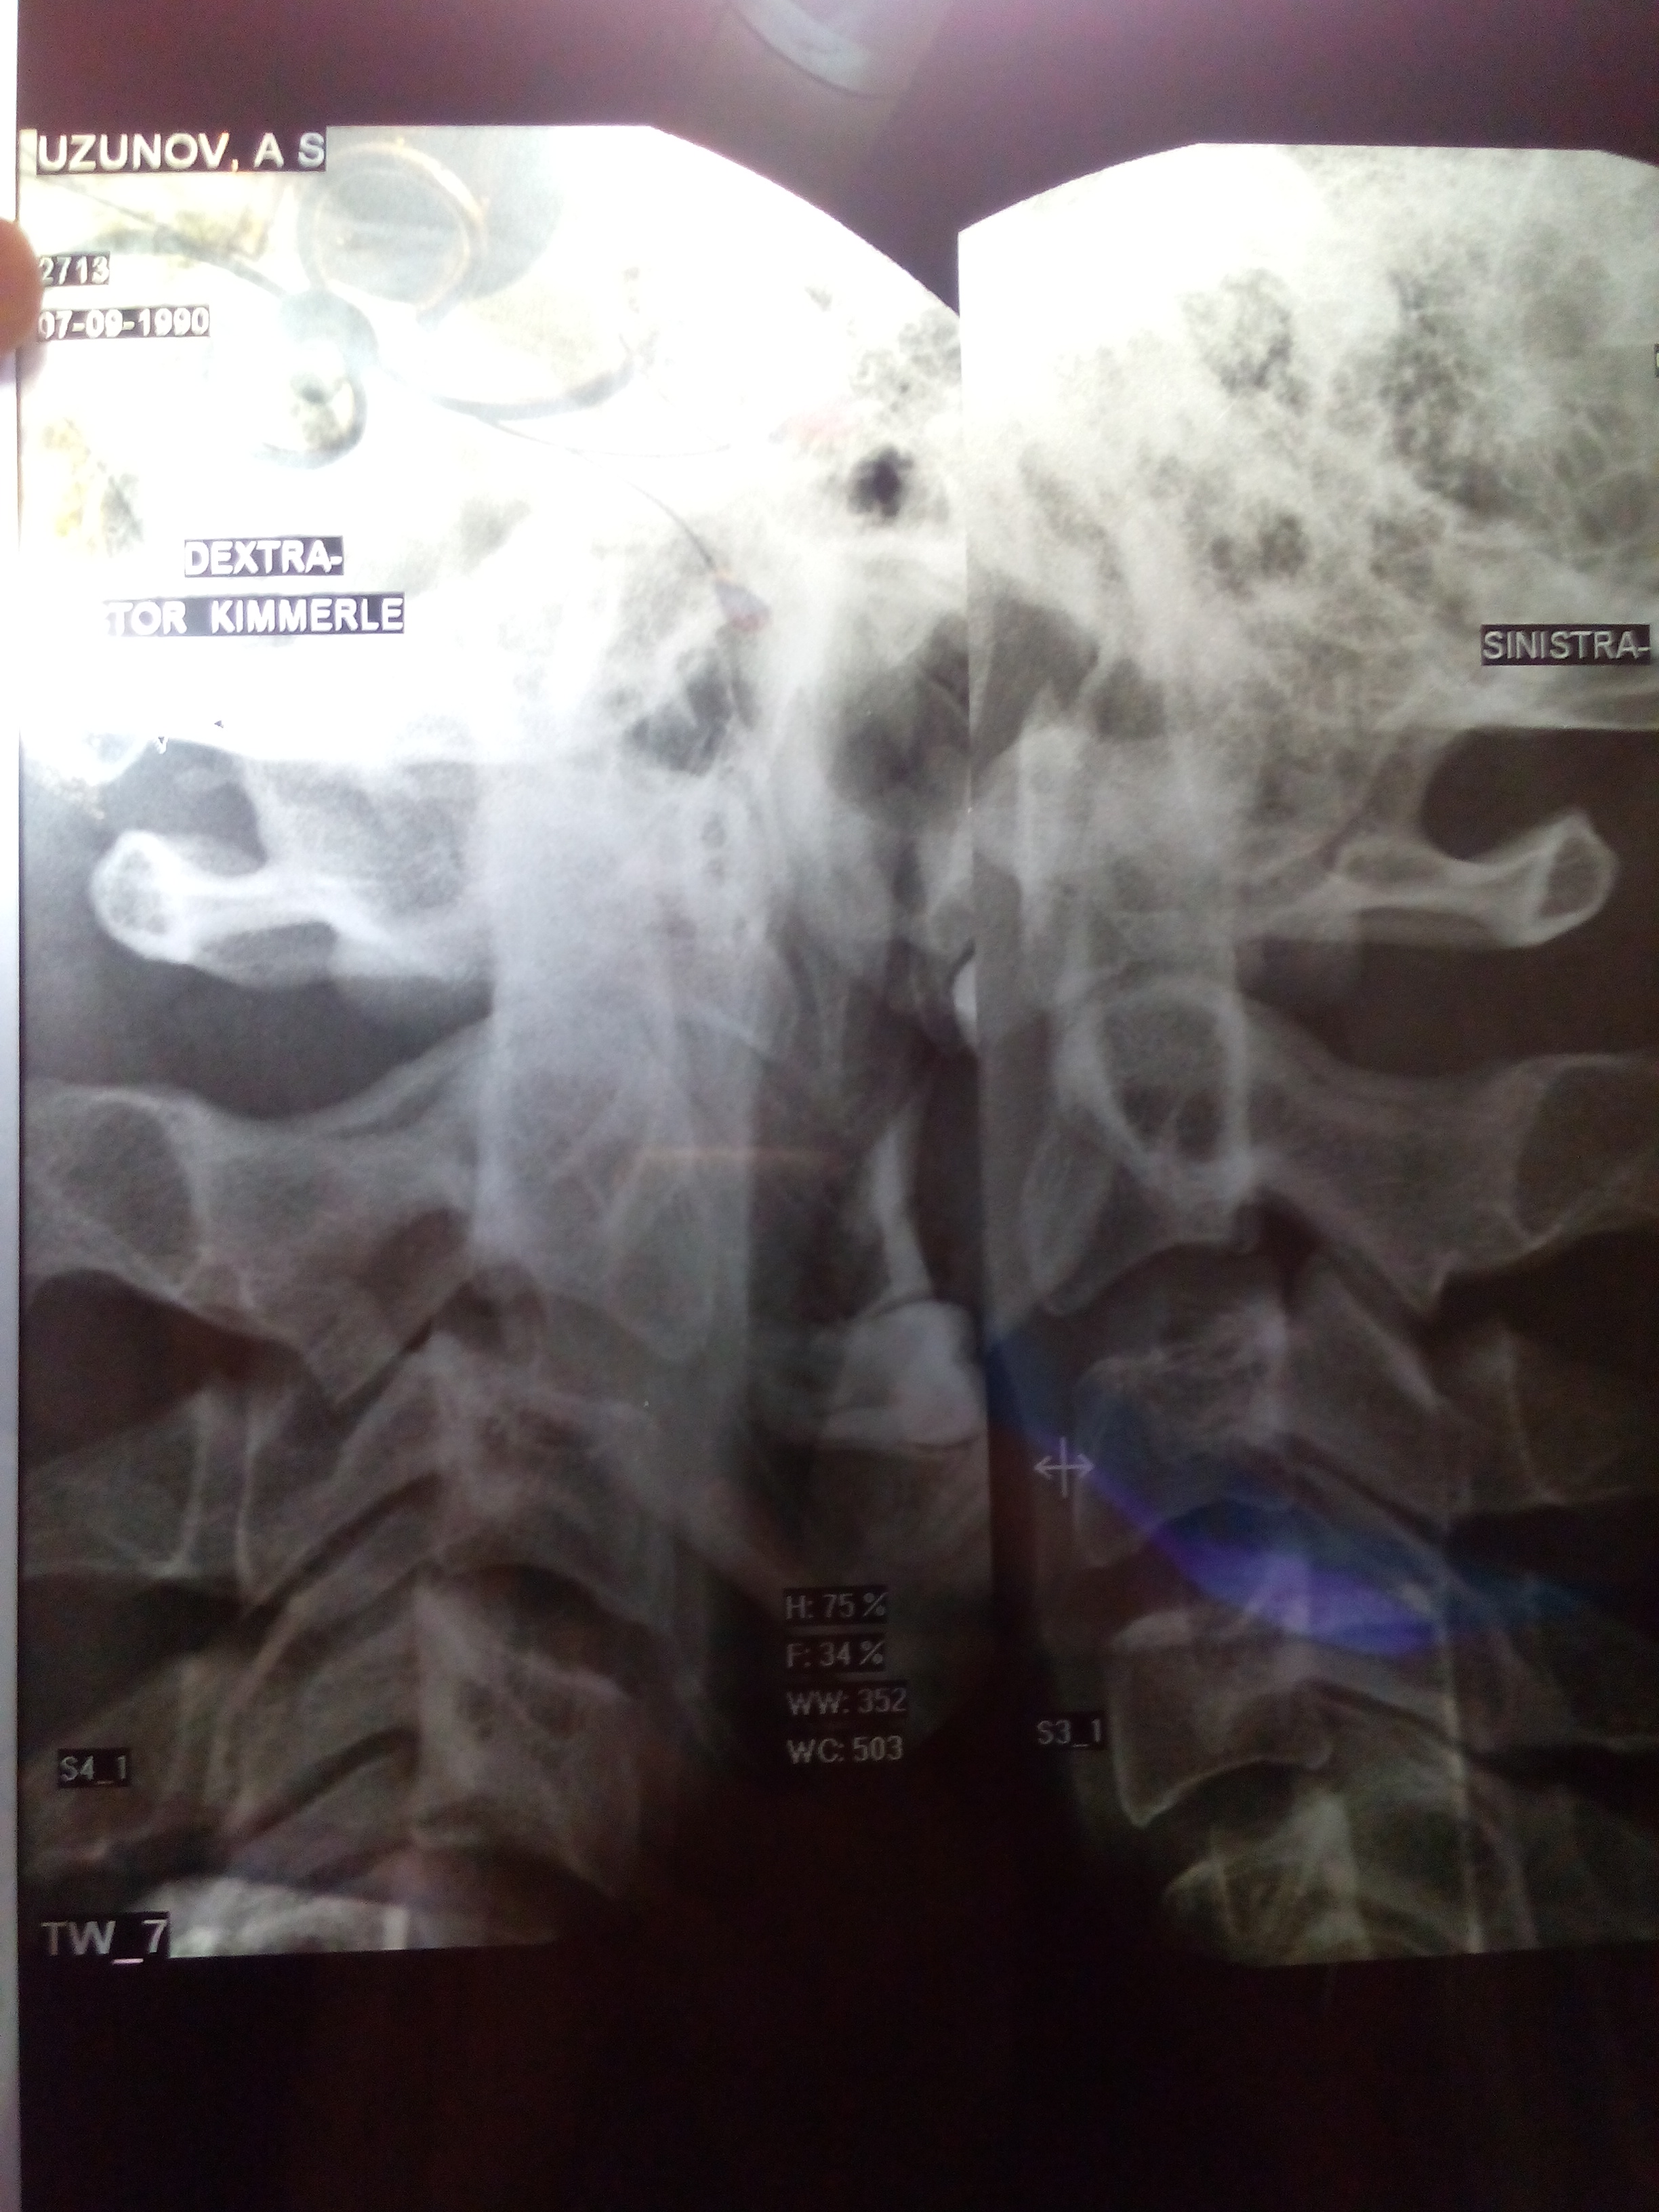

P.S. прилагаю снимки аномалии (простите за качество, я фотографировал снимки)

Снимок Кимерли 2015 г..jpg

Снимок Кимерли (2) 2015 г..jpg

Рентген 2015 (АНОМАЛИЯ).jpg

про снимки-аномалия не убедительна и ,как говорил, кт в данном случае более показателен.